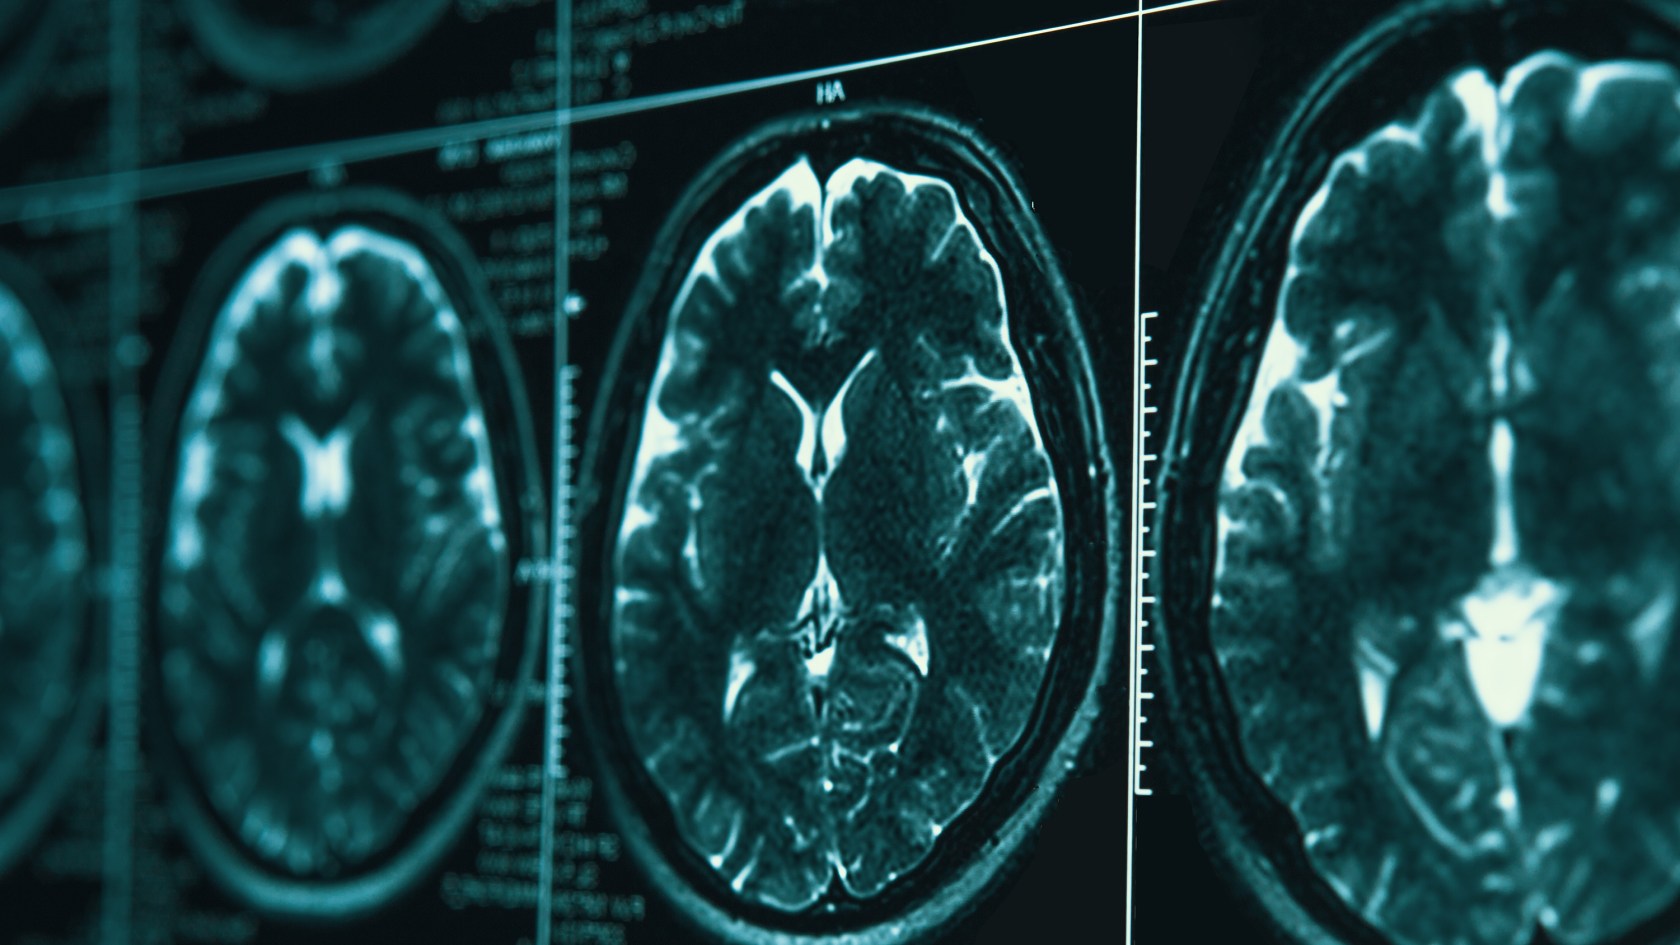

By the time symptoms begin creating problems, the disease has been unfolding in the brain for years. Microscopic amyloid-beta plaques have accumulated between neurons, and later threads of neurofibrillary tau proteins have tangled themselves into tight knots inside brain cells. The two abnormalities — first described in 1906 by the German physician Alois Alzheimer — have become the twin hallmarks of the disease.

But new technologies — artificial intelligence that may be able to identify new genetic determinants of the disease, blood tests for proteins in the brain, and real-time brain monitoring that reveals how individual neurons die — are finding new ways to understand and possibly help treat Alzheimer’s.